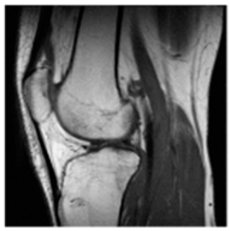

| Original Medical Images | |||||||

| Pair 1 | Pair 2 | Pair 3 | Pair 4 | ||||

![]() (1-9) PSNR = 44.14 | ![]() (1-10) PSNR = 41.90 | ![]() (1-11) PSNR = 40.09 | ![]() (1-12) PSNR = 41.41 | ![]() (1-13) PSNR = 42.24 | ![]() (1-14) PSNR = 40.35 | ![]() (1-15) PSNR = 40.79 | ![]() (1-16) PSNR = 40.84 |

| Shadow Images Produced by Using LSBs | |||||||

![]() (1-17) PSNR = 26.35 | ![]() (1-18) PSNR = 25.49 | ![]() (1-19) PSNR = 23.57 | ![]() (1-20) PSNR = 24.19 | ![]() (1-21) PSNR = 24.79 | ![]() (1-22) PSNR = 24.23 | ![]() (1-23) PSNR = 23.26 | ![]() (1-24) PSNR = 24.42 |

| Shadow Images Produced by Using Middle Bits | |||||||

![]() (1-25) PSNR = 18.97 | ![]() (1-26) PSNR = 19.95 | ![]() (1-27) PSNR = 14.10 | ![]() (1-28) PSNR = 13.84 | ![]() (1-29) PSNR = 16.66 | ![]() (1-30) PSNR = 13.23 | ![]() (1-31) PSNR = 13.38 | ![]() (1-32) PSNR = 14.75 |

| Shadow Images Produced by Using MSBs | |||||||